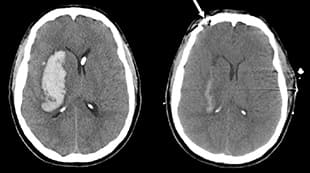

对中风说“不”!—来自UCLA Health医疗中心顶尖的神经科护理

根据美国疾病预防控制中心的定义,中风,也称为脑卒,发生在大脑部分的血液供应被阻塞或大脑的血管破裂时。任意一种情况都可能会导致大脑的某些部分受损或死亡。中风会导致持续性的脑损伤、长期残疾,甚至是死亡。